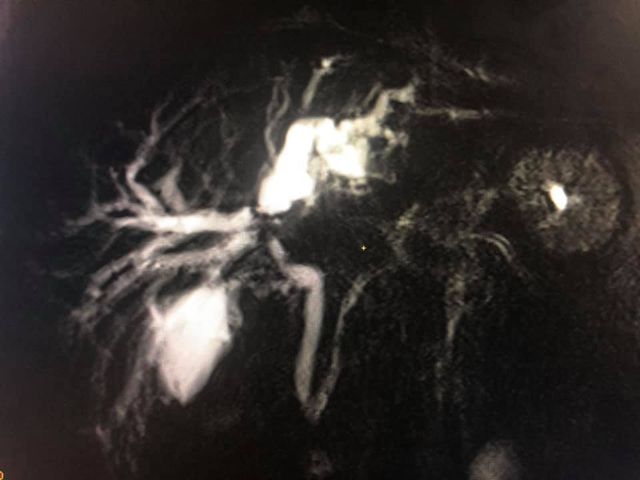

65 years of man type 3A hilar cholangiocarcinoma (complex hepatobiliary malignancy) with deep jaundice

SIX STEPS TO SUCCESS IN A ROLLER COASTER COVID CHALLENGE

- STEP 1: Left PTBD (to bring down jaundice)

- STEP 2: portal vein embolisation to allow growth of the small remnant left liver

- STEP 3: Right sided anterior and posterior PTBD to control persistent fever after initial intervention.

- STEP 4: admitted for surgery COVID positive CT CO-RADs 5 managed medically

- STEP 5: after 3 weeks waiting and repeat COVID PCR negative (couldn’t wait longer for risk of catheter dislodgement while waiting) underwent an Extended Rt hepatectomy with caudate lobectomy bile duct excision Left hepaticojejunostomy

- STEP 6: despite all the trials& tribulations and 7 hr surgery patient had a smooth recovery discharged by D6. An extremely satisfying result in a very difficult malignancy and a super motivated patient.